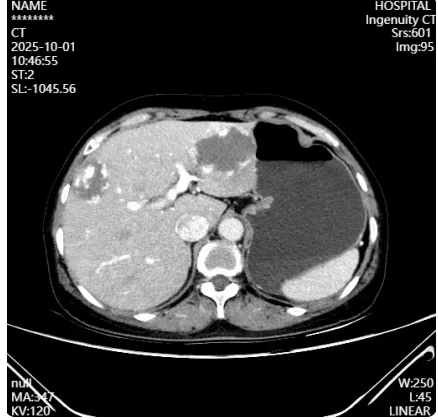

“肚子里揣着个‘大疙瘩’,夜里翻个身都提心吊胆,现在终于能睡踏实觉了!”刚能下床活动的陈女士(化名)抚摸着腹部微创小创口,脸上露出了久违的轻松笑容。今年50多岁的她,近期因反复的腹痛寝食难安,一次全面检查后,结果如晴天霹雳——肝左外叶和肝S8段各长了一个体积不小的血管瘤。

拿到报告的那一刻,陈女士的心里像压了块巨石。“血管瘤这么大,会不会恶变?该不该切?切了会不会伤身体?”一连串的疑问让她茶饭不思,思想负担越来越重。在家人的陪伴下,她辗转来到番禺区中医院就诊,接诊的赵理想副主任医师仔细研读各项检查报告,认为可以通过微创的方式解决病人的问题。当得知自己的病情无需通过传统大开刀手术治疗时,纠结多日的她终于下定决心:“我信你们,求你们帮我把这个‘心病’去掉!”